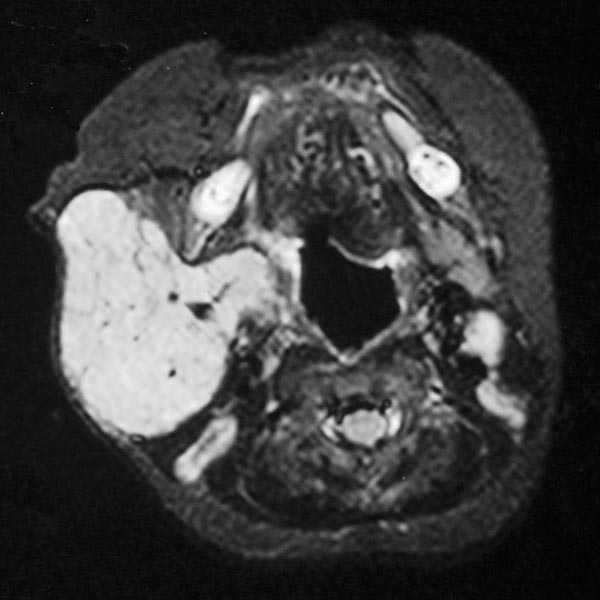

Transverse T1-weighted, non-enhanced MRI of the upper neck shows the tumor to be subcutaneously located, clearly solid, and sharply demarcated from surrounding tissue. The girl is now 12 months old, and the tumor has not regressed.

Transverse, T2-weighted, fat-saturated MRI of the upper neck again shows the subcutaneously located tumor very clearly as a hyperintense, sharply demarcated mass with central flow voids as a sign of intense arterial perfusion. Typical image of a subcutaneously located infantile hemangioma.